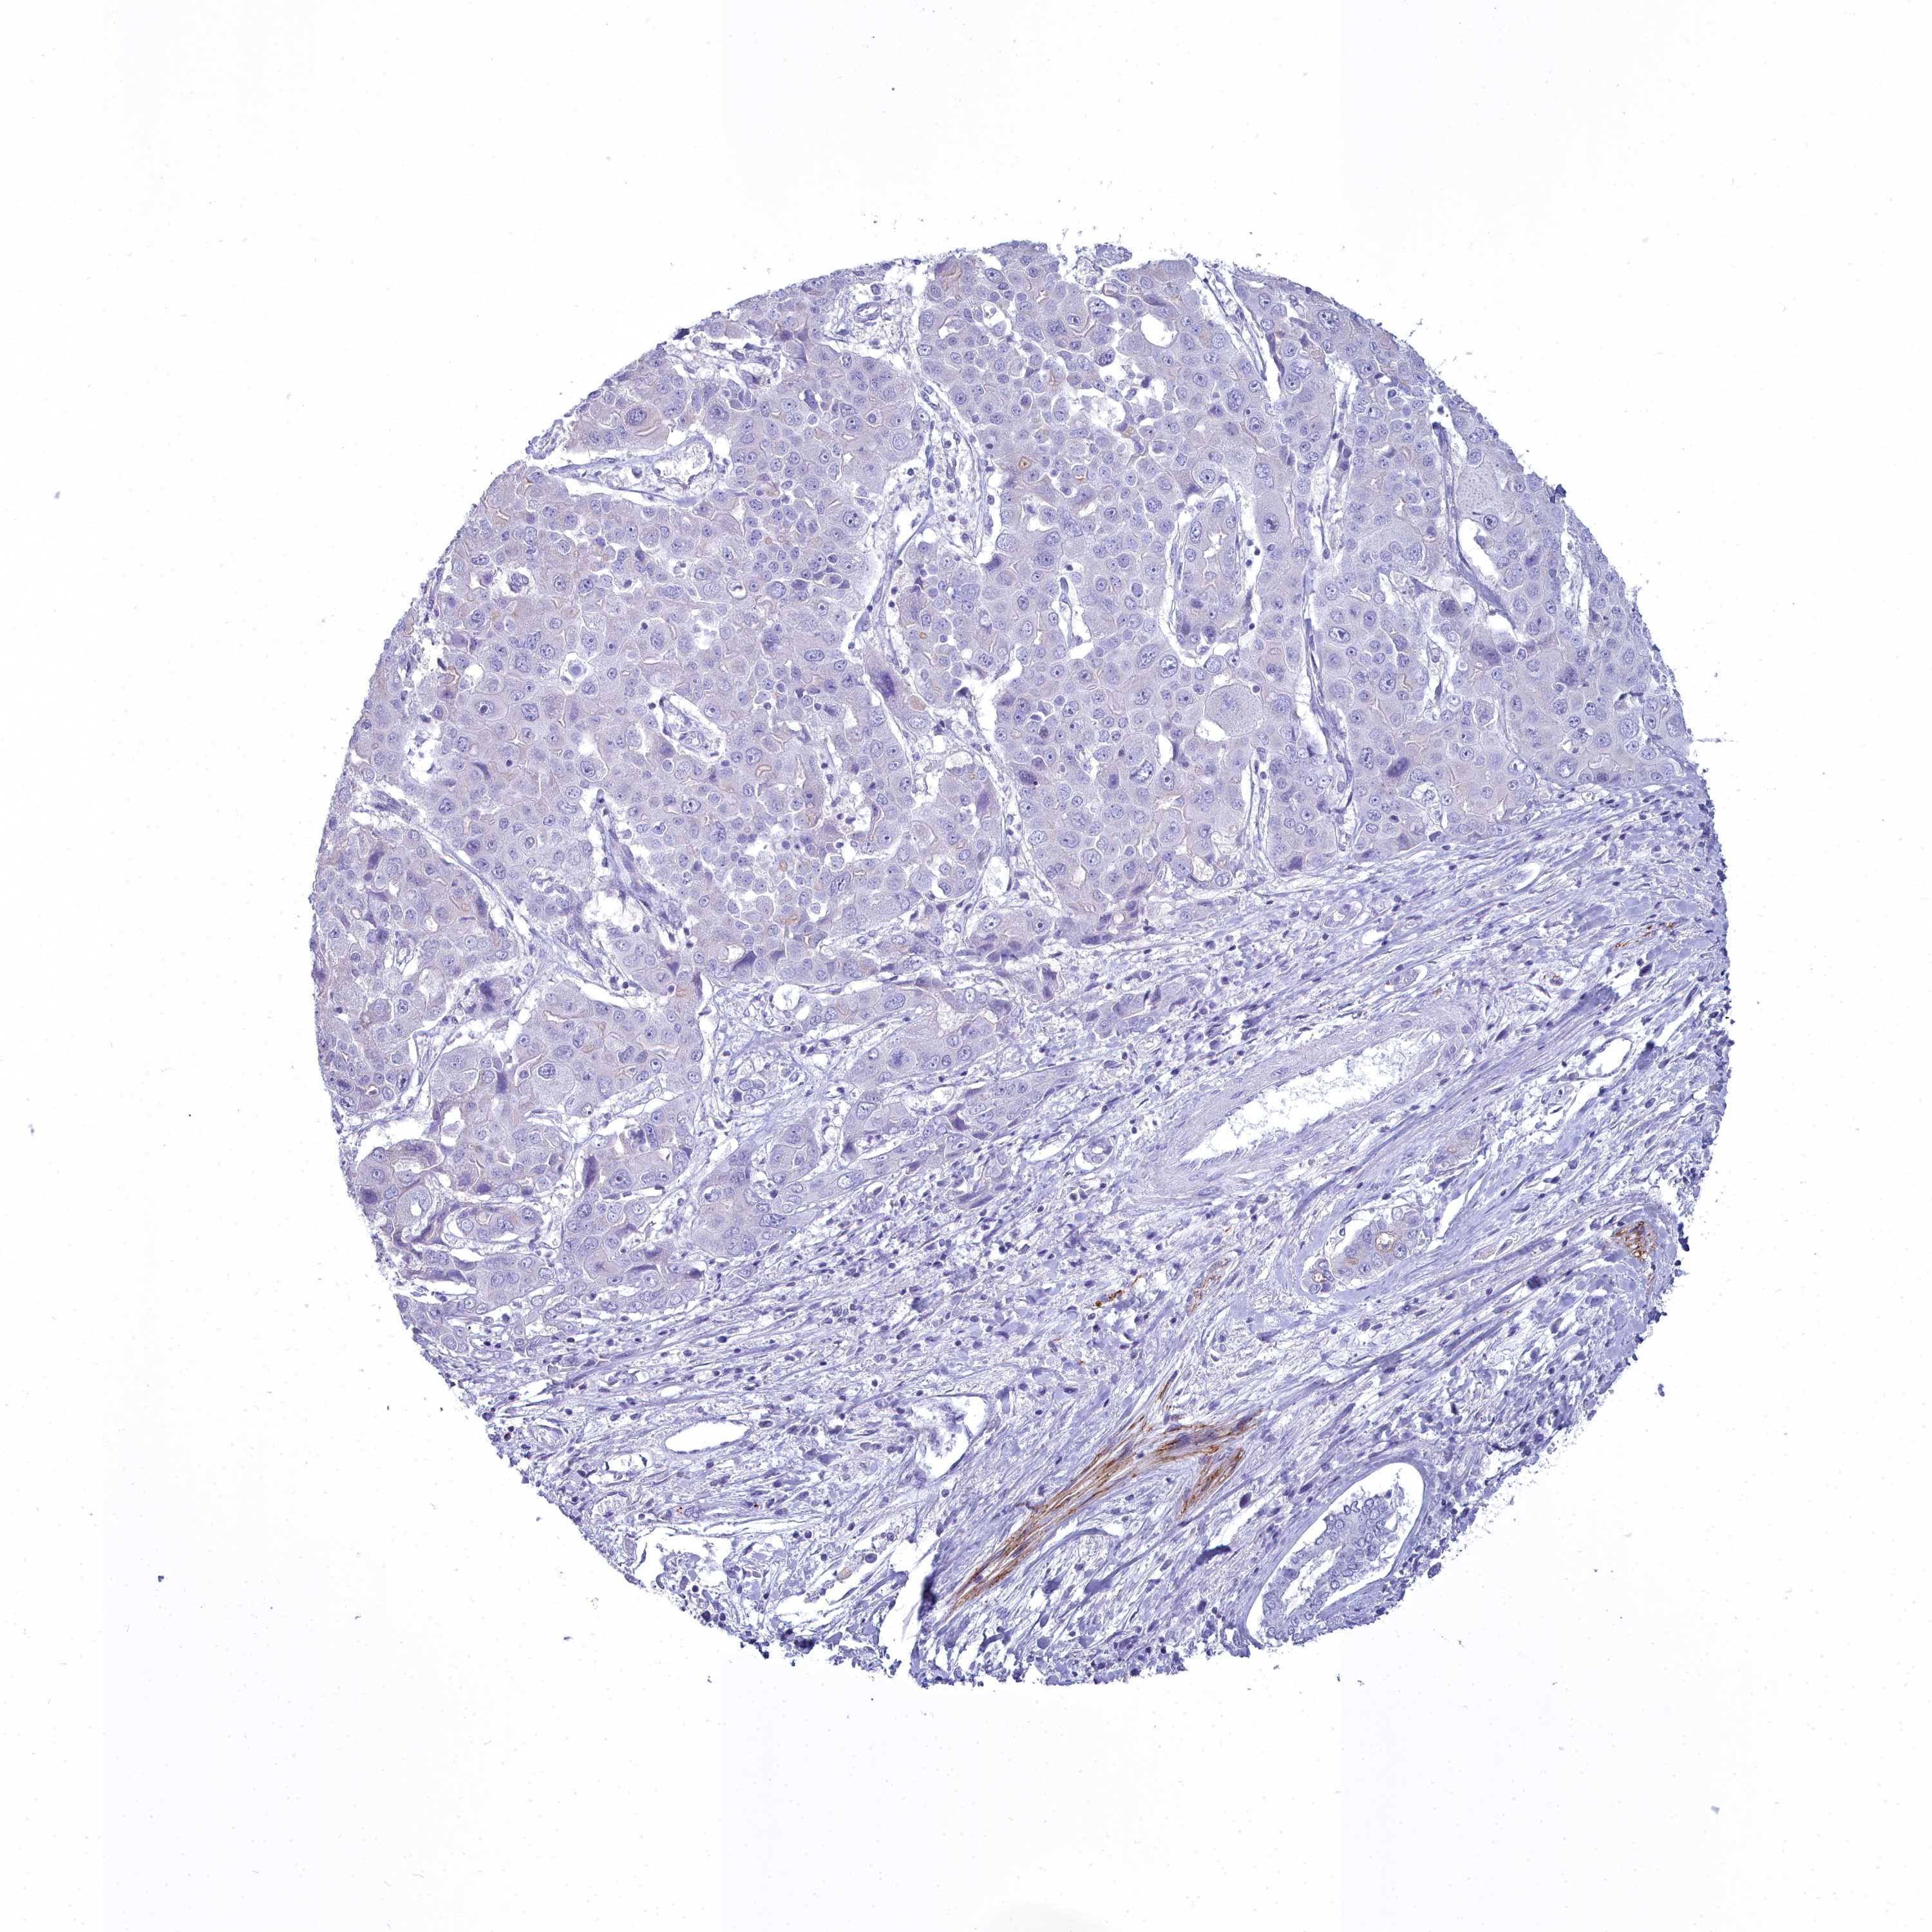

LIVER CANCER - Protein expressioni

A mouse-over function shows sample information and annotation data. Click on an image to view it in a full screen mode. Samples can be filtered based on level of antibody staining by selecting one or several of the following categories: high, medium, low and not detected. The assay and annotation is described here.

Note that samples used for immunohistochemistry by the Human Protein Atlas do not correspond to samples in the TCGA dataset.

Antibody stainingi

Antibody staining in the annotated cell types in the current human tissue is reported as not detected, low, medium, or high, based on conventional immunohistochemistry profiling in selected tissues. This score is based on the combination of the staining intensity and fraction of stained cells.

Each image is clickable and will lead to virtual microscopy that enables deeper exploration of all samples and also displays staining intensity scores, fraction scores and subcellular localization as well as patient and tissue information for each sample.

Antibody HPA039061

Antibody HPA039062

Antibody CAB015442

Antibody CAB022600

Cholangiocarcinoma

Carcinoma, Hepatocellular, NOS